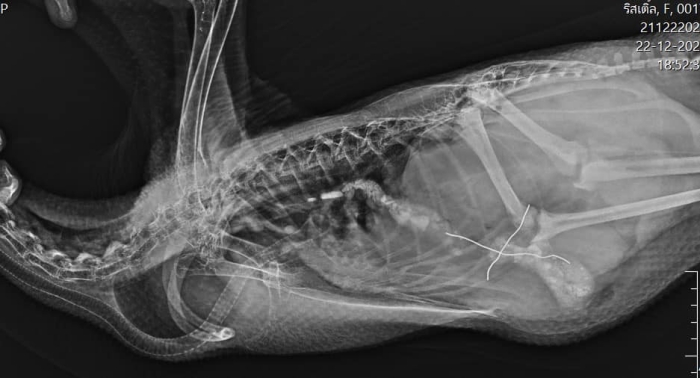

從醫院 Po 出的 X 光照中可以看到,電線卡在小女鵝的身體內,須得透過手術才能取出,因此院方對鵝鵝進行麻醉,將腹部的毛毛剃掉後實施開刀的動作。由於藥物的作用,小女鵝一臉生無可戀地攤平在手術床上,兩支「鳥仔腳」直挺挺的擺著,而一旁鵝爸爸心疼探頭查看女鵝的狀況,彷彿在對她叮嚀:「下次別再把什麼東西都放進嘴巴裡!」可愛又搞笑的場景讓網友都嘴角失守啦~